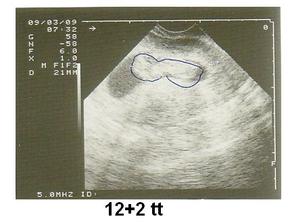

so.19.9.2009 40tt narodil se nám chlapeček Honzík v 11:25 hod. vážil 3900 g a měřil 53 cm